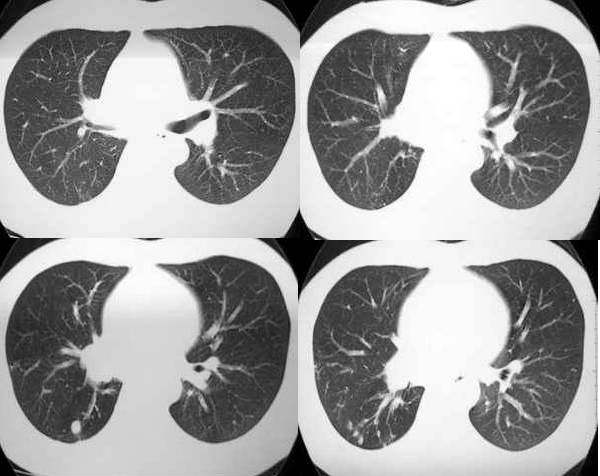

男,28岁,右胸不适,轻咳.余无特殊症状.请各位大侠发表见解

右肺下叶背段结核灶!肺门下方病灶没有传完整,不好说!看其形态,感觉象肺段实变,而且里面有散在点状钙化,不象是占位性病变.

28岁,右肺下叶背段病变,未见实质肿块,病灶内见钙化,及卫星灶,纵隔内有肿大淋巴结,结核吧,不象占位病变

右肺下叶背段结核灶,肺门软组织肿快影伴点壮钙化,考虑结核。纵隔淋巴结肿大。

右肺门区软组织肿块,边缘钙化,右肺中叶不张,右下叶背段结节状及斑片状影。首先考虑结核,建议支气管镜检查排除其他。

右肺门肿块,中叶支气管显示不清,纵隔肿大淋巴结。病人虽然年龄比较小。为什么不能考虑小细胞肺癌拌纵隔淋巴结转移?

右侧中间段支气管管壁增厚,管腔狭窄,形成块状软组织密度灶,右肺中叶膨胀不全,右肺下叶背段斑块状、片状阴影,且伴钙化,考虑:右侧中间段支气管内膜结核伴中叶不张、右肺下叶背段结核

右下叶背段及下叶内后基底段见斑点状及小片状影,有钙化。右下所谓的软组织密度影不在肺门,而是在下肺静脉层面以下,与膈相近,可能是横膈部分图像,图像没传完,易误导大家。综合考虑感染性病变(结核可能性大)